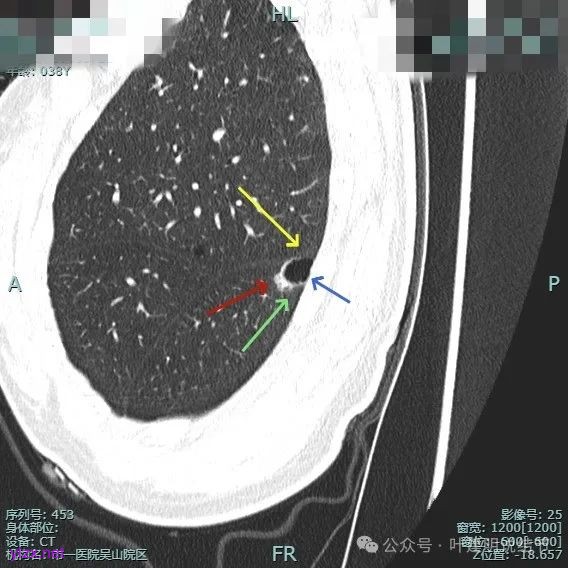

靶重建的影像上看,病灶的囊壁明显厚薄不均,有小血管进入,一侧的边似就是斜裂的样子。

囊壁有磨玻璃成分,边缘毛糙,有少许偏实性成分,仍有磨玻璃成分。

血管走向病灶,囊壁略不均。

此层见囊壁有较明显实性成分,血管进入明显。叶间裂侧平直。

混合密度,收缩力不明显,血管进入明显。

囊壁混合密度,整体轮廓清。

表面不平,血管进入,囊壁厚薄不均,紧贴叶间裂。

囊壁里面也有小空泡征。

混合密度但还是太致密,内壁毛糙不平。

病灶轮廓清楚,囊壁厚薄不均,贴着叶间裂与胸膜。

1、诊断问题:这是很典型的囊腔型肺癌,符合我自己之前提出的囊腔型肺癌三要素:(1)囊壁厚薄不均;(2)血管进入囊壁;(3)囊腔内壁不光滑(或再加止整体轮廓与边界较清)。而且由于囊壁实性成分明显,所以是有风险的,要及时干预处理。